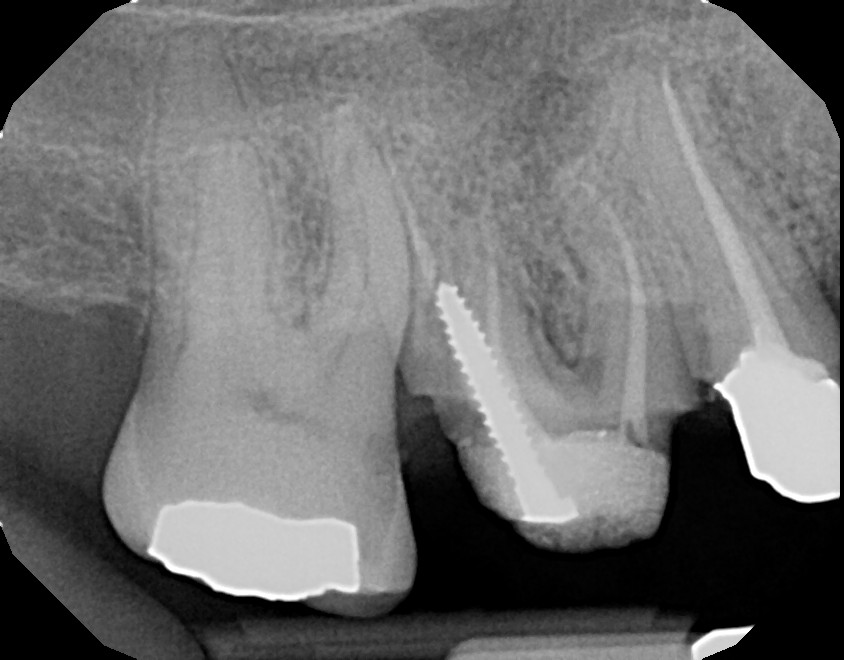

This is a root canal retreatment procedure of 2nd maxillary premolar (tooth #4) due to a missed canal which caused infection. An additional canal was located, both canals were retreated and the tooth will be restored with a crown. The first maxillary molar (tooth #3) needs to be retreated (redone) as well because of infection, due to inadequate root canal therapy. Always ask your general dentist for a referral to an endodontist (root canal specialist) for your root issues.